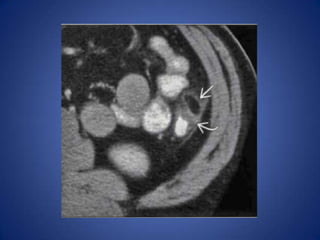

Urolithiasis

• Distal left ureteral stone may cause left lower

quadrant pain

• Diagnosis usually evident on CT

– Ureteral calculus, hydronephrosis, perinephric

stranding

Urolithiasis • Distal leftureteral stone may cause left lower quadrant pain • Diagnosis usually evident on CT – Ureteral calculus, hydronephrosis, perinephric stranding